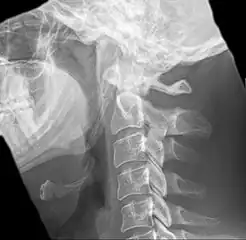

| Anteroposterior and lateral radiographs of cervical spine showing ossification of the stylohyoid ligament on both sides | |

Radiograph, lateral view showing elongated stylohyoid process and stylohyoid ligament ossification

Radiograph, lateral view showing joint-like formation in ossified stylohyoid ligament